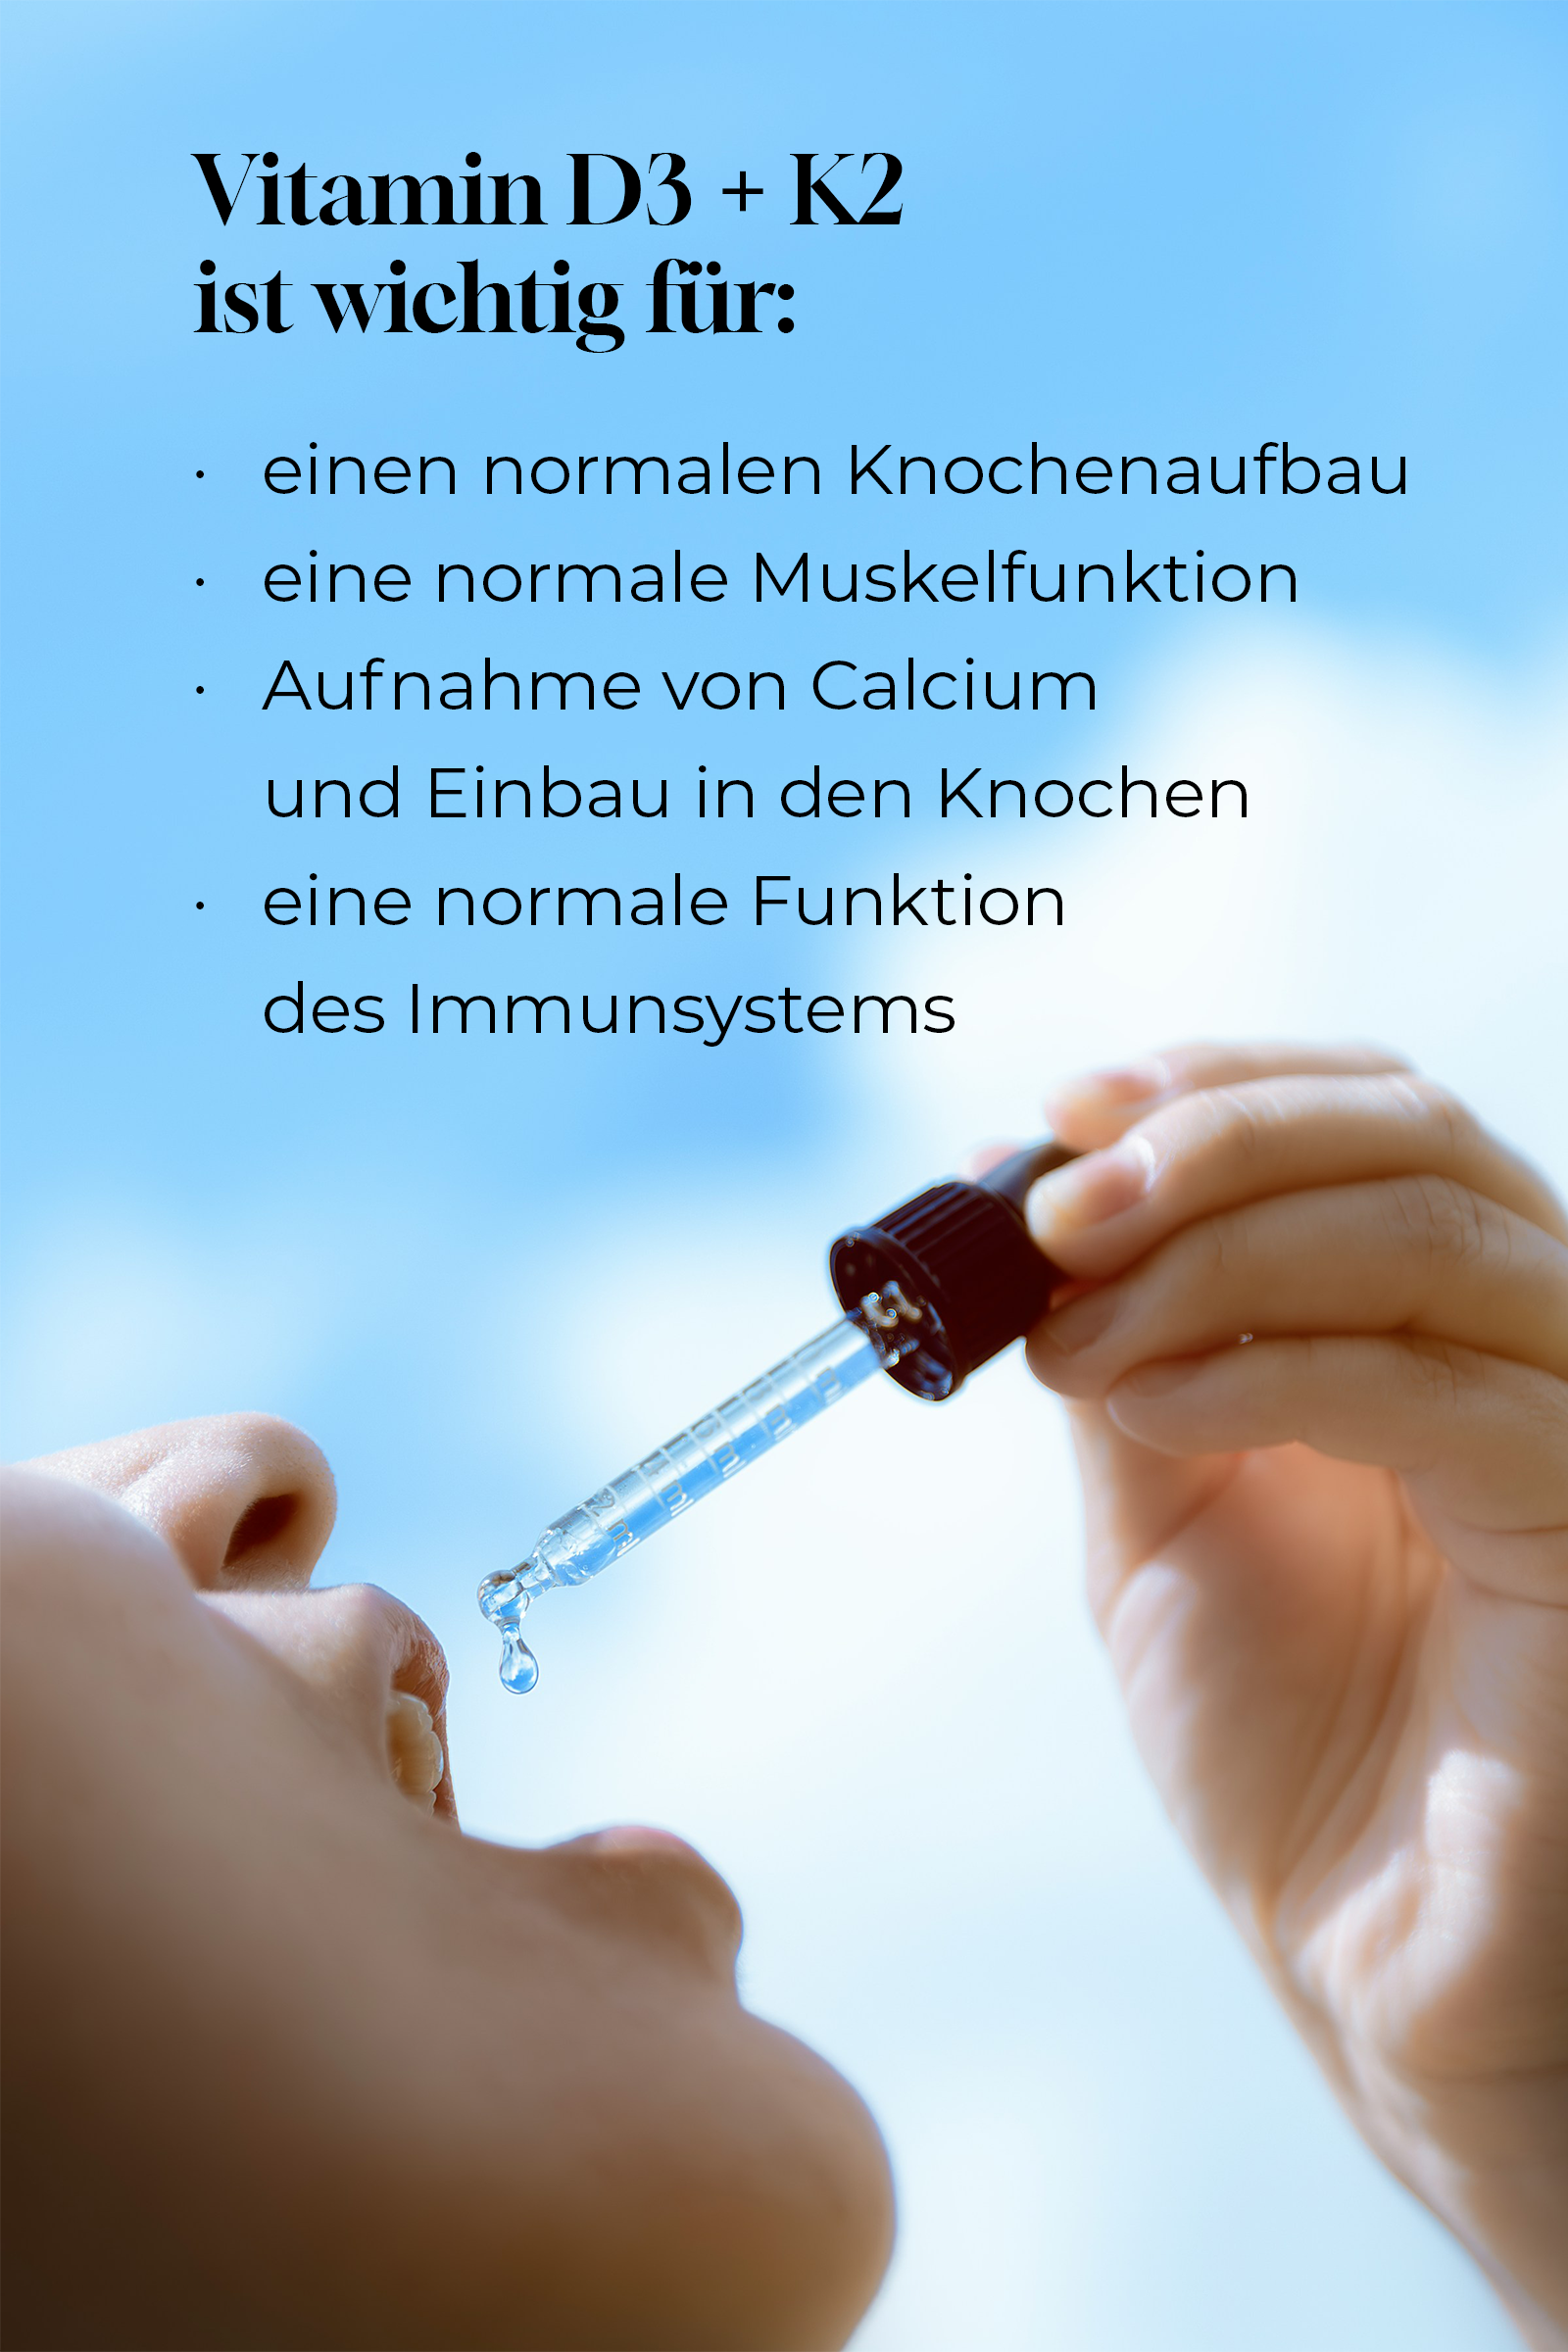

Vitamin D3 +k2

Vitamin D3 und Vitamin K2 spielen eine zentrale Rolle in der Regulation des Calciumstoffwechsels und der Knochengesundheit. Vitamin D3 (Cholecalciferol) ist für viele Körperfunktionen unverzichtbar – es unterstützt die Aufnahme und Verwertung von Calcium und Phosphor, reguliert den Blutspiegel dieser Mineralstoffe und beeinflusst so direkt die Stabilität von Knochen und Zähnen. Zudem wirkt Vitamin D3 auf Rezeptoren vieler Körperzellen, wodurch es das Immunsystem, die Muskelfunktion und die Zellteilung unterstützt.